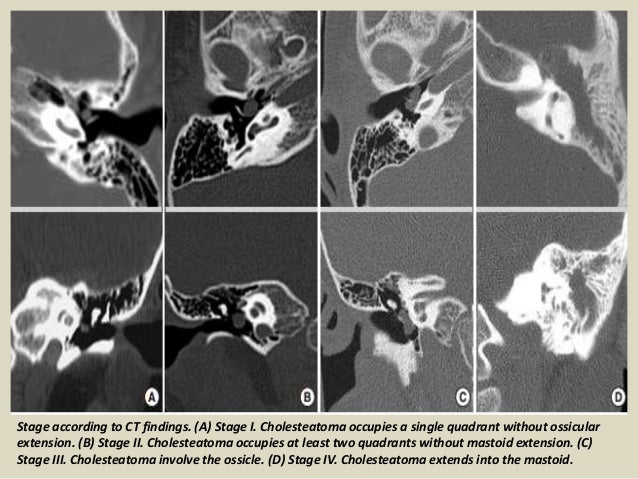

Presentation1 Pptx Radiological Imaging Of Choleteatoma